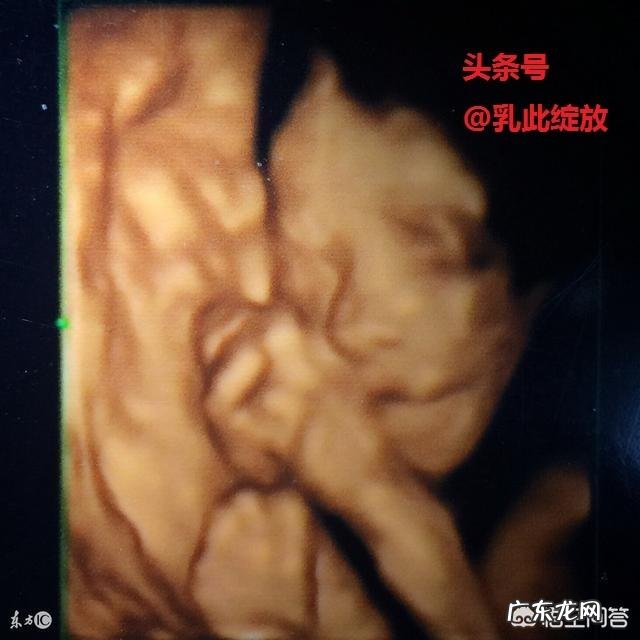

diyi:什么是四维彩超检查:

四维彩超,就是四维成像技术(4D),能直观、立体显示人体器官的三维结构及动态、实时地观察立体结构 。

【孕妇照四维需要在多少周以前呢?】第二:为什么做四维彩超:

四维彩超能够对胎儿进行超声检查能立体显示胎儿的颜色、面、各器官的发育情况,对胎儿畸形,如唇裂、腭裂、骨骼发育异常、心血管畸形等能早期诊断,早期筛查及早期zhi疗 。目前的胎儿医学,产前诊断等等 。

第三:做四维彩超的最佳时间:

孕12周至30周都可以做四维彩超检查 。但是受胎儿体位、胎盘、羊水等多因素影响,获取面部及内脏结构图像的最佳时间是20—28周 。

因此,建议在孕22周左右进行 。胎儿局部结构及运动状态清晰 。可发现严重的胎儿畸形有:无脑儿、严重脑膨出、严重开放性脊柱裂、严重胸膜壁缺损并内脏外翻、单腔心、致死性软骨发育不良等 。